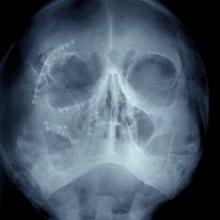

The surgeons who repaired her skull with titanium screws and knitted her flesh with hundreds of stitches, told the family her injuries were not from a fall, but consistent with being struck repeatedly with an object.